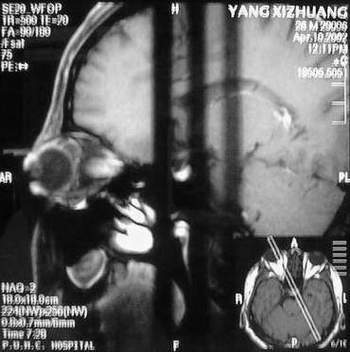

MRI及增强结果如下:

患者压颈及其它Valsava试验结果阴性。从MRI分析,在T1、T2、T+C检查该支血管均为明显流空现象,说明该血管血流速度很快,而从走行和分布看,眼上静脉可能性很大。也许也不能除外异常的眼动脉或异常血管。眶内主要可能的血管病变包括颈内动脉海绵窦瘘(高流窦)、AVM、眼眶静脉曲张、海绵状血管瘤、静脉性血管瘤、毛细血管瘤和眶内动脉瘤。。 1、颈内动脉海绵窦瘘:该患者临床有一部分支持该诊断。但从影像分析,海绵窦未见明显扩张;眼外肌未见明显充血扩张的长T1、长T2信号;颈内动脉海绵窦瘘常可见继发到血栓,可见到短T1、长T2的血栓信号。 2、眼眶静脉曲张:该疾患一般常见于小儿。该患大多数会出现Valsava试验阳性,间歇性突眼。不符合该患。影像学检查,于曲张静脉内常可见血栓和静脉石。所以不符合该患。 3、AVM:患者目前的影像学资料尚不全面,但可符合该诊断。临床上改病常见于30岁左右年轻人,单侧发病,于本患较符合。问题在于临床没有明确的血管杂音,似乎难以解释。 4、该患影像学与海绵状血管瘤差别很大,所以可基本排除此诊断。 5、静脉性血管瘤和毛细血管瘤:MRI中等T1、长T2信号,较易与本病鉴别。 6、眶内动脉瘤:我觉得患者并不能排除本病,但同样,由于波动性阴性,似乎也难以解释。 纵上所述:本人觉得,患者AVM可能性较大,同时不能除外眶内动脉瘤。 关于进一步检查,我觉得DSA价格过于昂贵。是否可先进行彩色多普勒检查,首先可以明确是静脉系统还是动静脉瘘抑或是动脉瘤。第二步,可进行MRA检查,可以清楚地显示海绵窦地相关关系,并可借此诊断或排除颈内动脉海绵窦瘘。如还需第三部检查,可进行MRV检查,对静脉系统进一步评价。三种检查总共的费用2000多圆,但给予我们的信息量已经很丰富了。 敬请各位医师提出自己的见解。 谢谢!